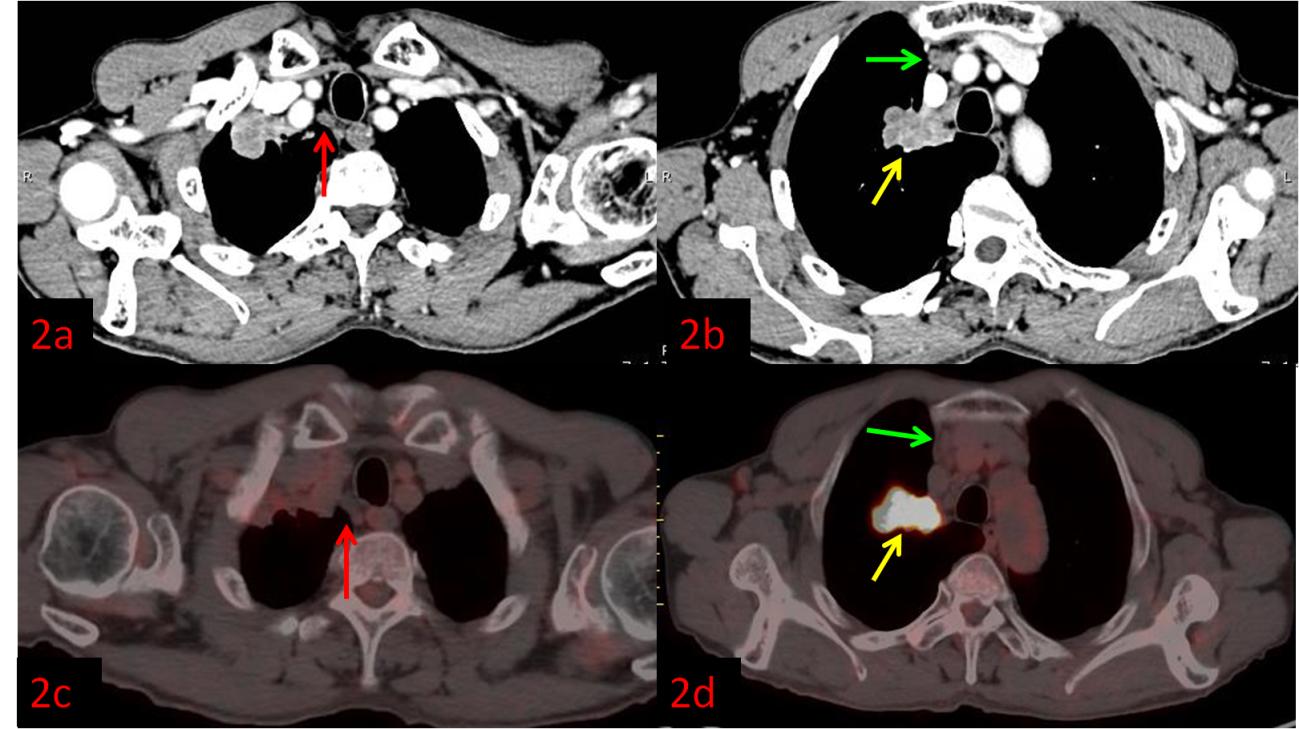

例2:老年男性,右肺上葉病變(黃箭)。強化CT示右上縱隔多發(fā)腫大淋巴結,不均勻強化,考慮轉移(圖2a紅箭、2b綠箭),初步分期為ⅢB,無法行手術根治。而PET/CT顯示淋巴結FDG代謝不高,考慮良性(圖2c紅、2d綠箭),患者分期降為ⅡB,于是進行了根治性手術。術后病理:右肺上葉鱗狀細胞癌,淋巴結均未見轉移。